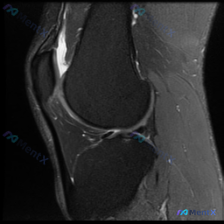

刚看到一个有意思的影像读片病例,整理了分析思路和大家分享一下。 病例基本情况 这是一张提供的单张膝关节矢状位MRI影像,用户核心疑问是:影像中是否存在软骨异常? 影像系统性分析 首先先确认影像基础信息: 1. 序列与定位:这张影像骨髓呈高信号,软组织对比度高,骨皮质为低信号,结构显示清晰,更倾向是T...